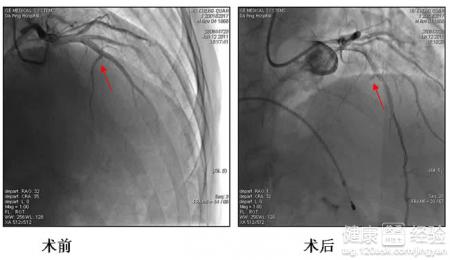

肥厚型心肌病是由常染色體顯性遺傳顯性遺傳造成的原發性心肌病,主要病理特征表現為心室壁非對稱性肥厚.心室腔縮小.左心室血液充盈受阻,主要臨床表現為勞力性呼吸困難.胸痛.心悸.心律失常.有的甚至病發有心力衰竭,心髒性猝死。在我國,發病率高,好發於男性青壯年,是青年男性致死的常見原因,肥厚型梗阻型心肌病是心肌病的一種類型。在用藥物治療無效的情況下,肥厚型梗阻型心肌病患者可做無水乙醇化學消融術或植入DDD型起搏器可能有效,在外科手術治療中切除最肥厚部分心肌是目前最有效的標准方案。

3對於非常嚴重的重症梗阻性肥厚型心肌病患者一般不采取手術治療。可做無水乙醇化學消融術或者植入術。外科手術最為有效的措施就是手術切除肥厚部分心肌最為有效,有的病人隨著病情的發展,伴有左心室擴張和心力衰竭,應用此種疾病的治療措施最為有效。